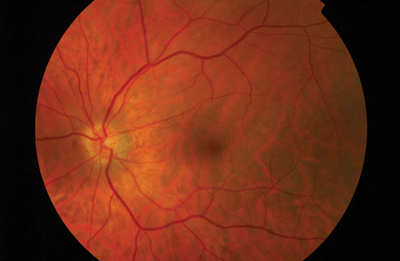

On a following visit to the macula clinic, patient underwent peripheral retinal examination which confirmed the presence of a shallow inferior retinal detachment in association with small infero-temporal U-tear. Interestingly, following the ranibizumab injections, macula appeared to re-attach. Patient was counselled about the findings and subsequently underwent left 23G pars plana vitrectomy, C2F6 gas and endolaser for repair of the retinal detachment. Following reattachment surgery the left eye did not show any signs of dry AMD (Figure 2). Retinal detachment (RD) is a recognised rare complication of intravitreal injections with an incidence of 0.013% [2]. However, the presence of a small post-oral u-tear typically seen in pseudophakic retinal detachments and the presence of inferior subretinal fluid bisecting the macula, were in keeping with a rhegmatogenous pathogenesis on presentation.

Figure 2 (top and above): Colour fundus photographs of both eyes following left retinal detachment repair.

Right macular shows glial scars from previous retinal detachment repair.